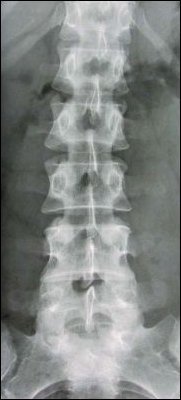

Passing small, highly controlled amounts of radiation through the body and capturing the resulting shadows on a digital screen creates an x-ray image. Doctors commonly order plain x-rays of the spine. This examination takes 10-15 minutes to complete.

After registering with the receptionist, you may be asked to change into a gown. You will be taken to an x-ray room where several x-ray pictures will be taken. You may be asked to hold your breath for some of the pictures. If you are having x-rays of the neck, 5-7 pictures will be taken. It is customary to take 3 pictures of your mid-back. Two to six pictures of the low back are usually taken. Tailbone (sacrum and coccyx) x-rays usually require 2-3 pictures. You will have to wait while the pictures are checked. A repeat picture is occasionally required.